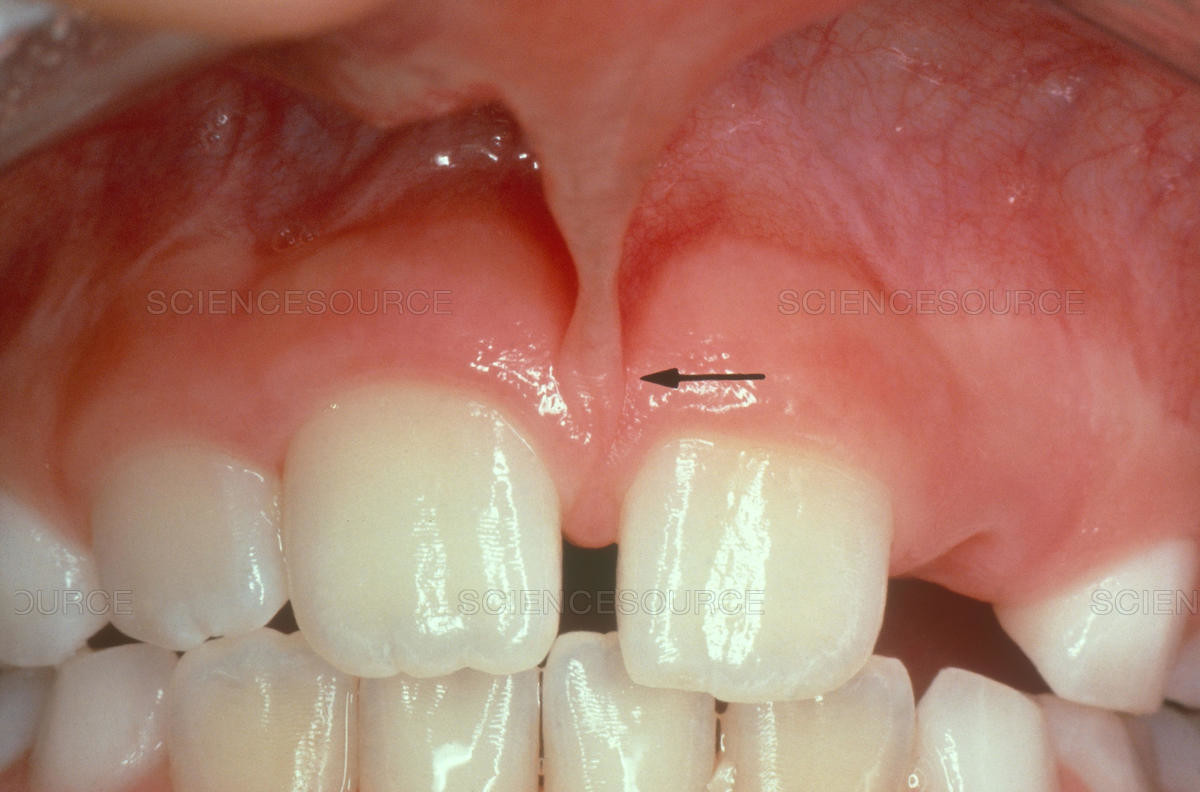

Frenulum In The Mouth

What Is A Frenum (Frenulum)?

In our mouth, most people have two groups of tissue called frenums found in and around the gums and teeth. It is a piece of really soft tissue that appears as a thin line between the gums and lips. You can find it on the top and the bottom of your oral cavity. There’s also a frenum that extends along the bottom of the tongue and connects to the bottom of the mouth just behind the teeth. Different people have different frenums. It can vary in length and thickness.

Types Of Frenum

There are two basic types of frenums in your mouth:

Labial frenum – This type of frenum is placed in the front of your mouth between the upper lip and gum. His counterpart is positioned between the lower gum and the lower lip. If there is an issue with this type of frenum, it can change the way your teeth grow in and can influence your dental health. Particularly it can pull your gums away from a tooth revealing the root.

Lingual frenum – This type of frenum is located between the floor of your mouth and the base of your tongue. It comes in different sizes and sometimes it can limit the movement of your tongue. This means frenum is tight, and we call this condition: tongue-tie. If this happens, it can affect the way the tongue moves in your mouth. This problem is especially annoying for babies because it makes it hard for a baby to feed properly.

Possible Problems With Frenum

The main purpose of a frenum is to give the lower and upper lip, as well as the tongue proper support and more stability in your mouth. If you suffer from an oversized frenum, it can lead to various problems that can affect your teeth, gums, and mouth.

Some of the conditions you may encounter if there’s an issue with a frenum include:

·  frenum tear

· developmental malformations in your mouth

· trouble with swallowing

· speech difficulties if the tongue is tight

· disruption of the healthy growth of your upper two front teeth, which may cause a gap

· mouth breathing and snoring, due to deformities in jaw development created by abnormal frenum growth

· problems with nursing, due to lip-tie or tongue-tie in infants

· the gap formed between front teeth

· the difficulty of fully stretching your tongue

· receding of gum tissue away from the root of the teeth and revealing the tooth root.